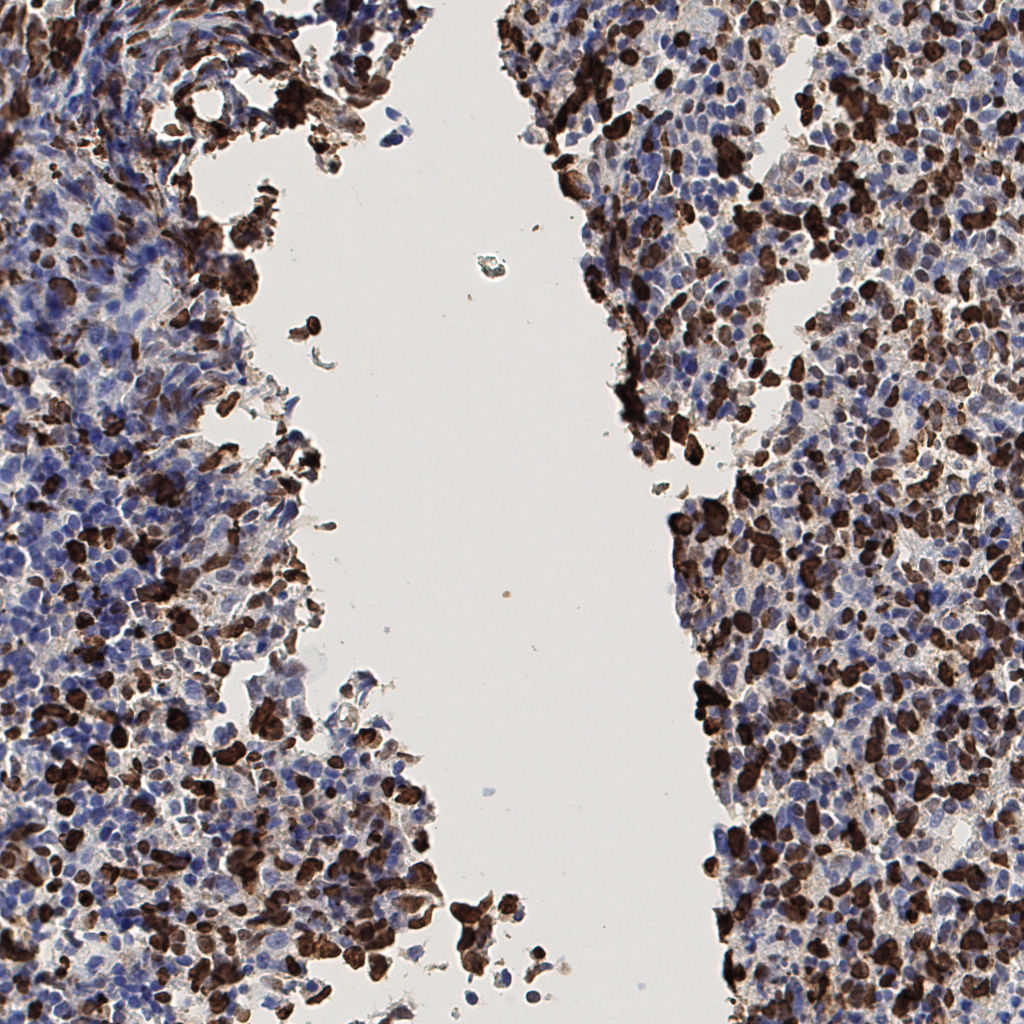

7.85%

Ki67 指数

阴 1104 阳 94

H255858-KI-67.ndpi